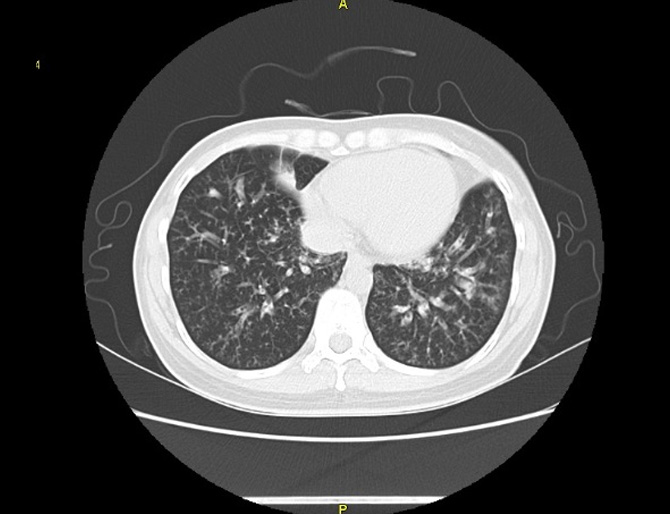

기관지확장증의 CT 사진